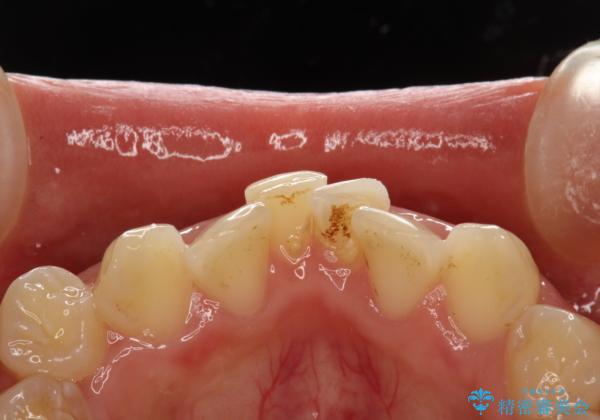

矯正治療開始前のPMTC

- 矯正治療前にステインを取りたいとのことで来院されました。ステインは前歯のみだったため、PMTC30分コースを行いました。

PMTCとは、歯科の専門家が器械を使用して行う歯のクリーニングのことです。普段の歯磨きでは取り切れない溝、キワなどの細かい部分も徹底的に除去します。ステインや歯石などが付着したままだと、虫歯や歯周病の発見がしずらいことがあります。特に矯正治療前には、念入りな虫歯や歯周病チェックが必要なため、PMTCでしっかりと汚れを除去しておくことが大切です。